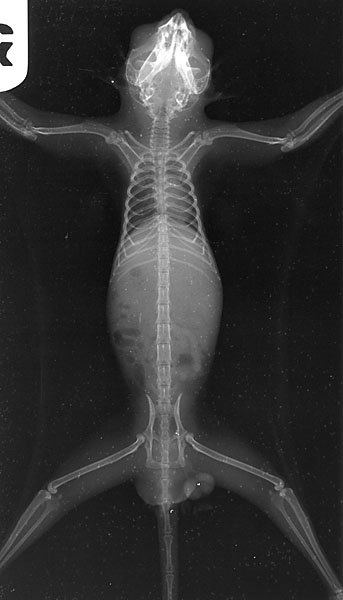

正常のレントゲン写真

X線検査で骨の薄さと変形、骨折の有無などを確認します。